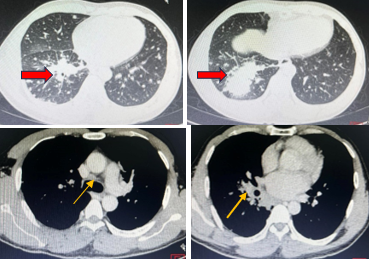

Cắt lớp vi tính lồng ngực (5/4/2019):

Hình 3:  Hình ảnh khối u thuỳ dưới Phổi phải, kích thước 70×75 mm (mũi tên đỏ) nhiều tổn thương thứ phát 2 phổi, hạch trung thất và rốn phổi phải (mũi tên vàng)